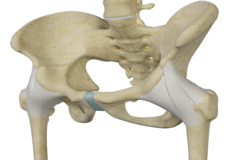

The hip joint is the junction where the hip joins the leg to the trunk of the body. It is comprised of two bones: the thigh bone or femur and the pelvis which is made up of three bones called ilium, ischium, and pubis. The ball of the hip joint is made by the femoral head while the socket is formed by the acetabulum. The Acetabulum is a deep, circular socket formed on the outer edge of the pelvis by the union of three bones: ilium, ischium, and pubis. The lower part of the ilium is attached by the pubis while the ischium is considerably behind the pubis. The stability of the hip is provided by the joint capsule or acetabulum and the muscles and ligaments which surround and support the hip joint.

The head of the femur rotates and glides within the acetabulum. A fibrocartilagenous lining called the labrum is attached to the acetabulum and further increases the depth of the socket.

The femur or thigh bone is one of the longest bones in the human body. The upper part of the thigh bone consists of the femoral head, femoral neck, and greater and lesser trochanters. The head of the femur joins the pelvis (acetabulum) to form the hip joint. Next, to the femoral neck, there are two protrusions known as greater and lesser trochanters which serve as sites of muscle attachment.

- Ligamentum teres: This is a small ligament that extends from the tip of the femoral head to the acetabulum. Although it has no role in hip movement, it does have a small artery within that supplies blood to a part of the femoral head.

- Acetabular labrum: The labrum is a fibrous cartilage ring which lines the acetabular socket. It deepens the cavity, increasing the stability and strength of the hip joint.